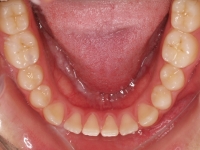

El paciente E.A. acude a nuestra consulta por diastema inferior y ausencia de contactos en los sectores laterales.

Chica de 17 años tratada en 1 año con stripping en los dientes inferiores